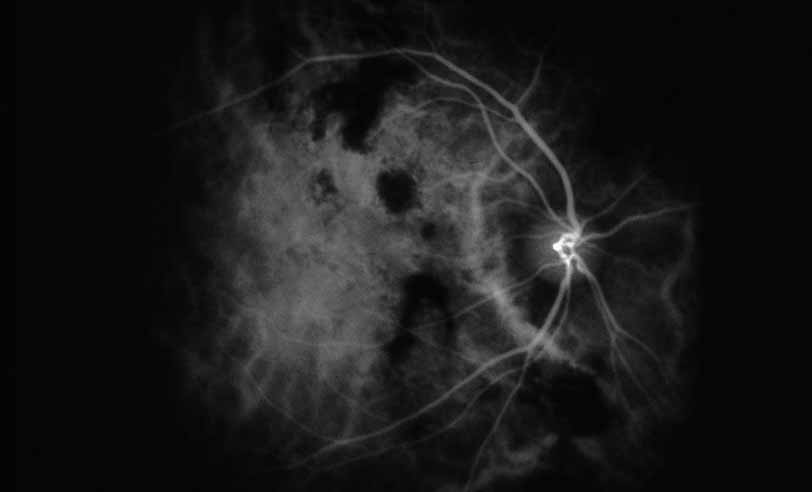

A third instance in which fluorescein angiography concentrating on the optic nerve may be helpful is in eyes with vascular engorgement of the optic nerve, especially with media opacities. Fluorescein angiography may help the clinician distinguish abnormally leaking capillaries from neovascularization. In acute multifocal hemorrhagic retinal vasculitis, optic nerve involvement is common in the early stages of the disease, 47 with optic nerve disc neovascularization seen later (see Figs. 10, 11, 12, and 13). Another fluorescein angiographic clue to the distinction between optic disc vessel engorgement and true neovascularization is the presence of associated large zones of retinal capillary nonperfusion such as those seen in sarcoidosis (see Figs. 14 and 15),34–40 acute multifocal hemorrhagic retinal vasculitis (see Figs. 10 and 11),47 or Eale disease (see Figs. 16 and 17).48–52

Fig. 11 Acute multifocal hemorrhagic retinal vasculitis. Fluorescein angiogram confirms the presence of associated retinal capillary non-perfusion without neovascularization at the onset of the disease.